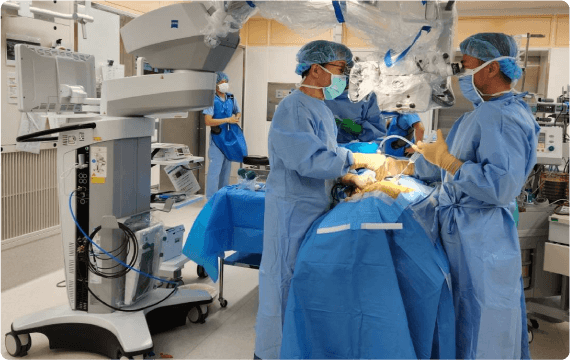

手術・麻酔

シムラ病院では増え続ける手術件数に対応できるよう、手術室を3部屋に増設しました。整形外科領域においては、広島大学四肢外傷講座と連携し、一般外傷から難易度の高い外傷手術まで幅広い整形外傷手術医療を提供しています。また、低侵襲で最先端の高度診療技術を活用した脊椎手術には自信があり、人工関節・スポーツ外傷に至るまで様々な分野における質の高い手術をお約束いたします。

外科領域においては広島大学病院と連携し、呼吸器外科(肺)手術、乳腺手術、一般外科手術も行っており、多くの患者さまに喜んでいただいています。

手術に麻酔は不可欠です、麻酔管理は、手術中の患者さまの痛みをなくし適切に眠った状態にするだけでなく、血圧や脈拍、呼吸を調整して、全身状態を良好に維持する医療行為です。また、手術中だけでなく術後も痛みを和らげ、患者さまを肉体的・精神的な負担から守ります。当院では、麻酔科専門医が患者さまの全身状態を術前に評価し、最適な麻酔法を提供しています。また全身麻酔に様々な種類の区域麻酔(超音波装置を用いて神経の走行に沿って局所麻酔薬を注射する方法)を併用して、術中、術後の痛みの緩和を実施しています。術後の痛みが強い手術では、痛み止めが常に流れる装置をつけて、薬剤師や看護師とのチームで管理して早期回復を目指します。

シムラ病院では増え続ける手術件数に対応できるよう、手術室を3部屋に増設しました。整形外科領域においては、広島大学四肢外傷講座と連携し、一般外傷から難易度の高い外傷手術まで幅広い整形外傷手術医療を提供しています。また、低侵襲で最先端の高度診療技術を活用した脊椎手術には自信があり、人工関節・スポーツ外傷に至るまで様々な分野における質の高い手術をお約束いたします。

外科領域においては広島大学病院と連携し、呼吸器外科(肺)手術、乳腺手術、一般外科手術も行っており、多くの患者さまに喜んでいただいています。

手術に麻酔は不可欠です、麻酔管理は、手術中の患者さまの痛みをなくし適切に眠った状態にするだけでなく、血圧や脈拍、呼吸を調整して、全身状態を良好に維持する医療行為です。また、手術中だけでなく術後も痛みを和らげ、患者さまを肉体的・精神的な負担から守ります。当院では、麻酔科専門医が患者さまの全身状態を術前に評価し、最適な麻酔法を提供しています。また全身麻酔に様々な種類の区域麻酔(超音波装置を用いて神経の走行に沿って局所麻酔薬を注射する方法)を併用して、術中、術後の痛みの緩和を実施しています。術後の痛みが強い手術では、痛み止めが常に流れる装置をつけて、薬剤師や看護師とのチームで管理して早期回復を目指します。